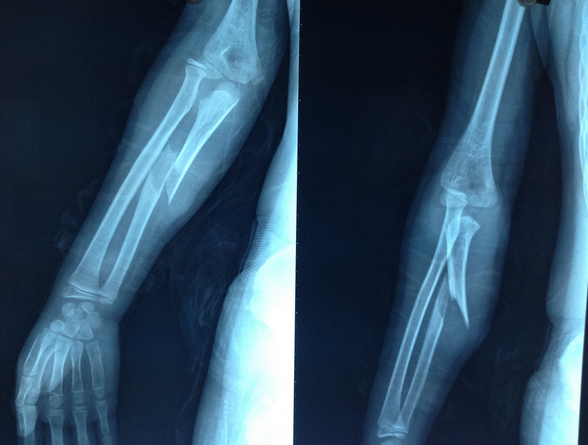

临床诊断冠状突骨折时常采用CT、X线片以及三维重建这三种影像学检查。

CT检查冠状突骨折时能够清晰地辨别出骨折的位置、骨折粉碎的程度以及骨折线的走向等,但是在直观性与整体性方面有所欠缺。

X线片检查冠状突骨折时相较于CT检查,其整体性与方便性较高,检查人员能够直观的看到患者冠状突骨折以及周围组织损伤的情况,方便医生作进一步的诊断。但是X线检查仍存在一些不足,当冠状突的体积较小时,如果有重叠遮挡的情况,通过X线很容易发生漏诊的情况;如果患者冠状突骨折伴有其他肘关节组织损伤,X线不容易辨别骨折块的来源;X线无法实现全方位观察关节面,使得检查人员能够观察的角度受限。

与CT检查和X线检查相比,三维重建在检查冠状突骨折时具有较好的优势,它不仅能够直观的看到骨折特征,还能从不同的角度来观察骨折的形态,提高了医生对冠状突骨折的分型、诊断与评估的准确性。